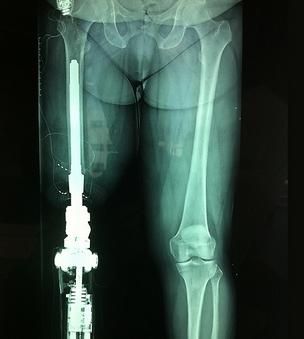

在中國,需要假肢醫療設備的人有很多,但是傳(chuan) 統假肢造價(jia) 高,還容易引起並發症,導致這一需求長時間得不到完善的解決(jue) 。好在近些